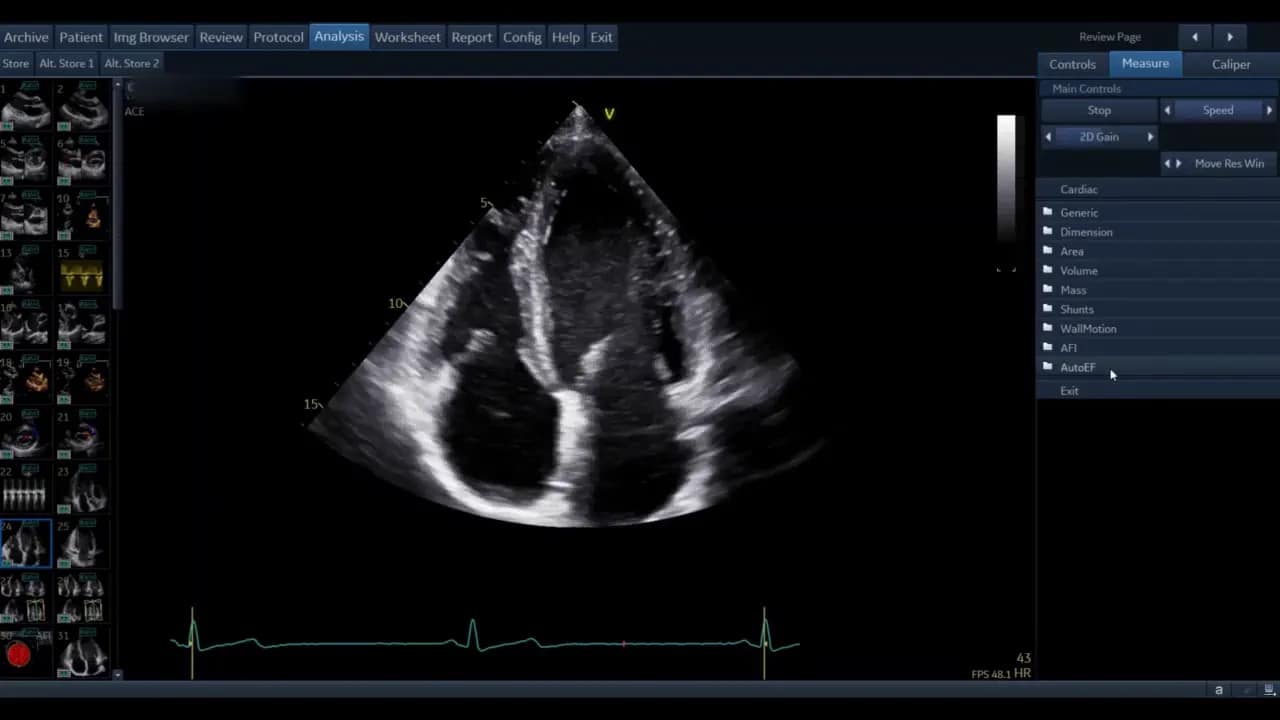

Öffnen Sie eine gespeicherte apikale Ansicht und wählen Sie die Mess‑Funktion. Navigieren Sie im Menü zur AutoEF‑Option und starten Sie das Tool.

In aktuellen Versionen (abhängig von Modell und Softwarestand des Ultraschallgerätes) nutzt AutoEF eine View‑Recognition KI im Hintergrund. Diese findet automatisch die geeignetsten Vierkammer‑ und Zweikammer‑Bilder für die Analyse. Falls die automatische Erkennung fehlschlägt oder eine ältere Softwareversion verwendet wird, werden Sie aufgefordert, die Ansicht manuell zu wählen und zu kennzeichnen.

Wenn Sie manuell wählen müssen, markieren Sie zunächst die Vierkammer‑Ansicht, sofern diese als erstes analysiert werden soll. Die korrekte Kennzeichnung von septal, lateral und dem zugehörigen Piktogramm ist wichtig. Prüfen Sie, ob die Beschriftung mit der angezeigten Ansicht übereinstimmt, andernfalls zurück zur Auswahl und richtig taggen.